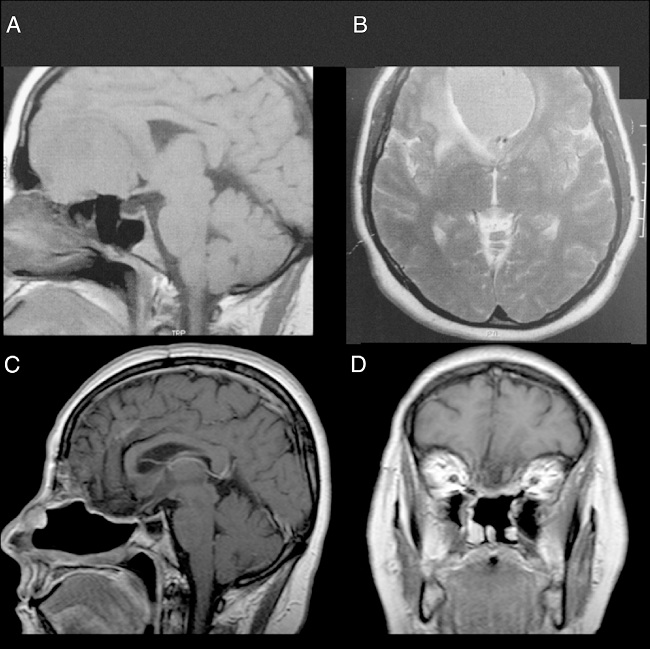

Female, 49 years old, complaining of diminished olfaction and cognitive changes (periods of disorientation and confusion and memory impairment). Magnetic resonance imaging (MRI) showed a large intracranial mass, with dural attachment and tail on top of the cribriform plate, occupying most of the anterior skull base with significant mass effect and oedema in both frontal lobes (Fig. 1).

Male, 39 years old, complaining of mild to moderate frequent headaches and diminished olfaction. MRI showed an intracranial mass with dural attachment on top of the cribriform plate with bone invasion of the plate and the ethmoid (Fig. 2).

Both patients had anosmia after the procedure as expected for a transcribriforme approach, but were free of recurrence and without any signs of brain herniation through the bone defect on magnetic resonance imaging (Figs. 1,2 and 6).